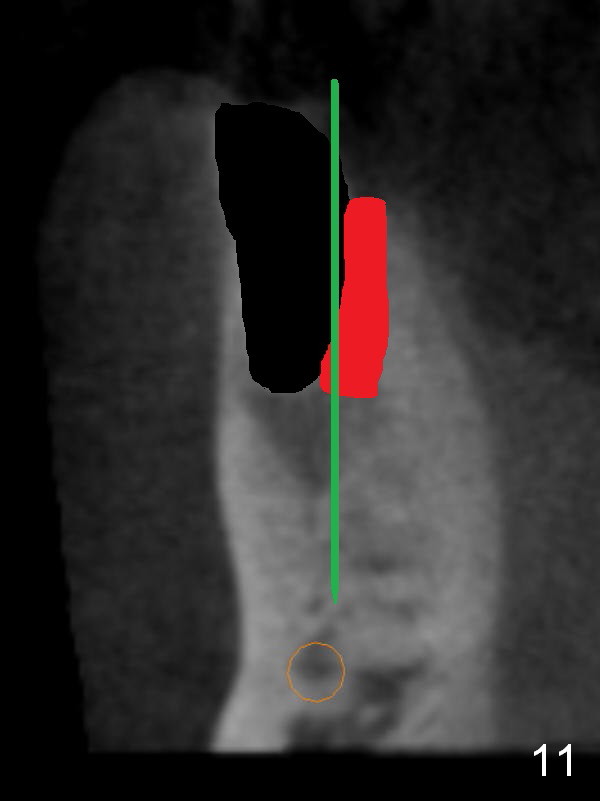

CT sagittal section shows that it is possible to place 4.5x20 mm implant (Fig.6). Axial (Fig.7) and coronal (Fig.9) sections show that the lingual (L) plate is much thicker than the buccal (B) one. To prevent the implant being buccally deviated, a Lindermann bur is used after extraction (black area in Fig.8,10) to remove ~ 1mm bone from the lingual plate (red area in Fig.8,11). A 2 mm pilot drill is placed as lingual as possible (green in Fig.8,11). If the implant (Fig.12) starts to deviate buccally while being placed, remove it from the osteotomy and remove more bone from the lingual plate. Place the implant again and monitor the trajectory tightly.